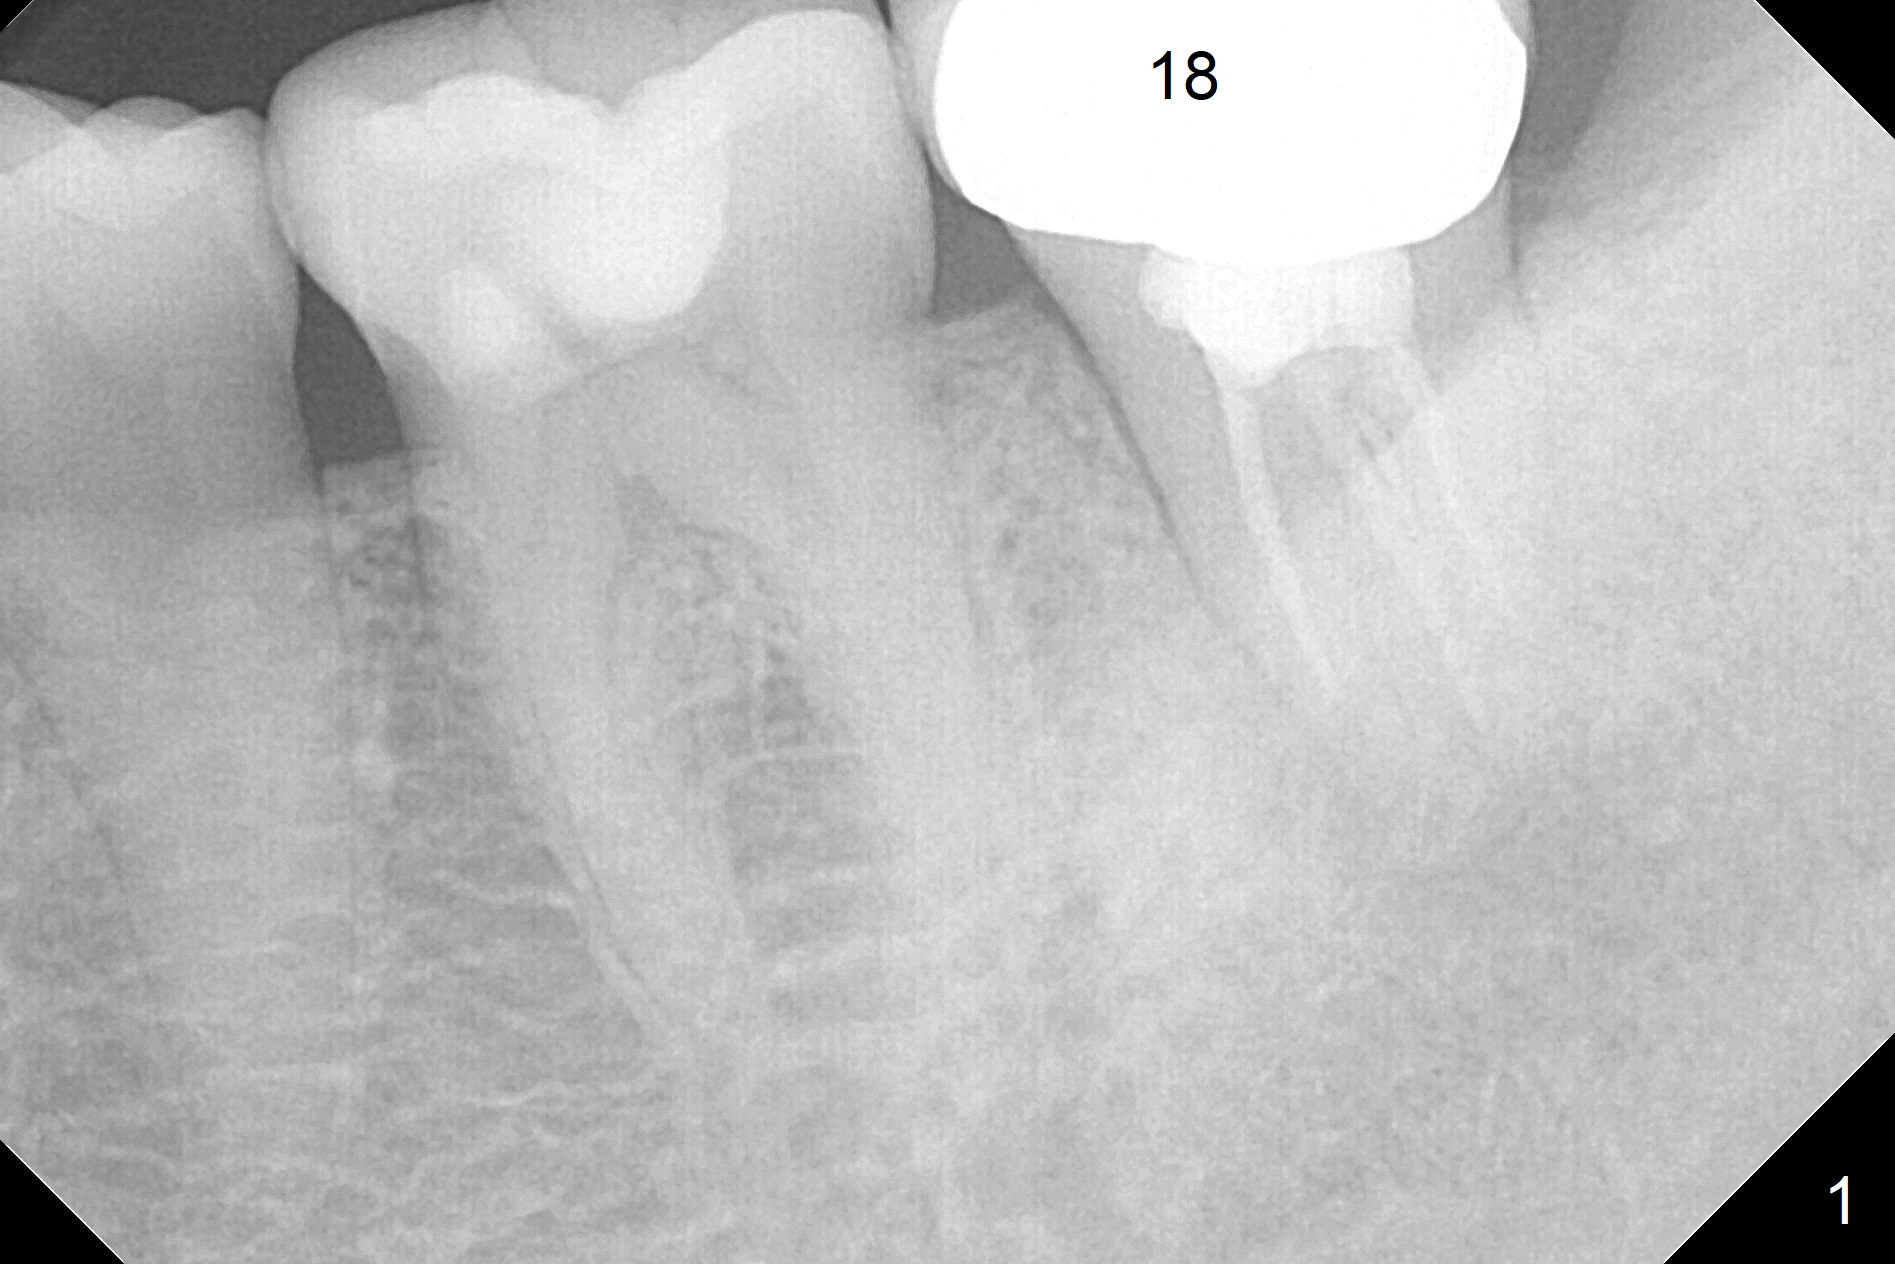

A 32-year-old woman has a buccal fistula after RCT (Fig.1). She would like to have extraction and implant to eradicate the lesion. In addition, there appear to be several canals which need to be retreated. Since the Inferior Alveolar Canal (IAC) is indistinct, osteotomy and implant placement will be confined 1-2 mm beyond the socket after debridement (Fig.2). Take the 1st intraop PA as early as possible (after use of 2 mm Bicon drill with extension and insertion of marked parallel pin). Osteotomy is buccal (if the buccal plate defect is not severe), as the IAC is lingual at this site. Also consider initiate osteotomy in the mesial slope of the socket. Prepare Sinus Master Kit for possible use of its short stoppers (2-6 mm).